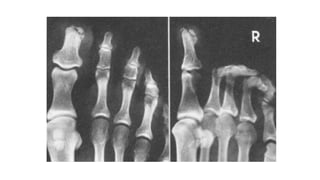

JUANETE

CUERNO CUTANEO

GOTA

PIE DIABETICO